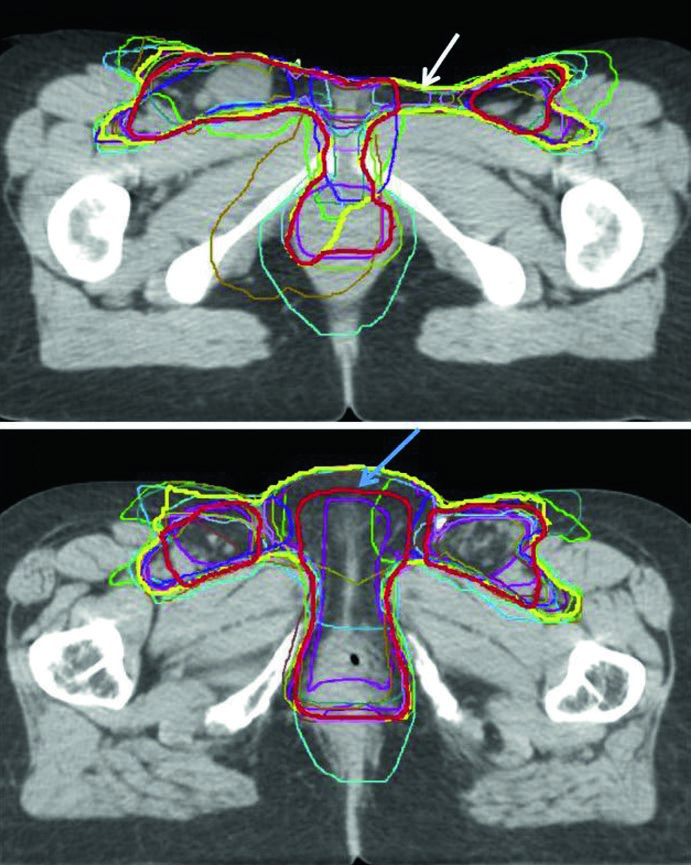

A Fig. 23.3 acrescenta um ponto que costuma passar despercebido: mesmo entre especialistas em IMRT há variabilidade relevante no contorno. O consenso aparece em amarelo, o consenso modificado em vermelho e os contornos individuais de 14 médicos aparecem sobrepostos em dois casos, um localmente avançado e outro pós-operatório. O consenso modificado foi retraído do espaço entre vulva e virilha e também da superfície cutânea quando essas áreas foram consideradas de baixo risco. Em outras palavras, reduzir volume é possível, mas apenas quando o raciocínio de risco é explícito.